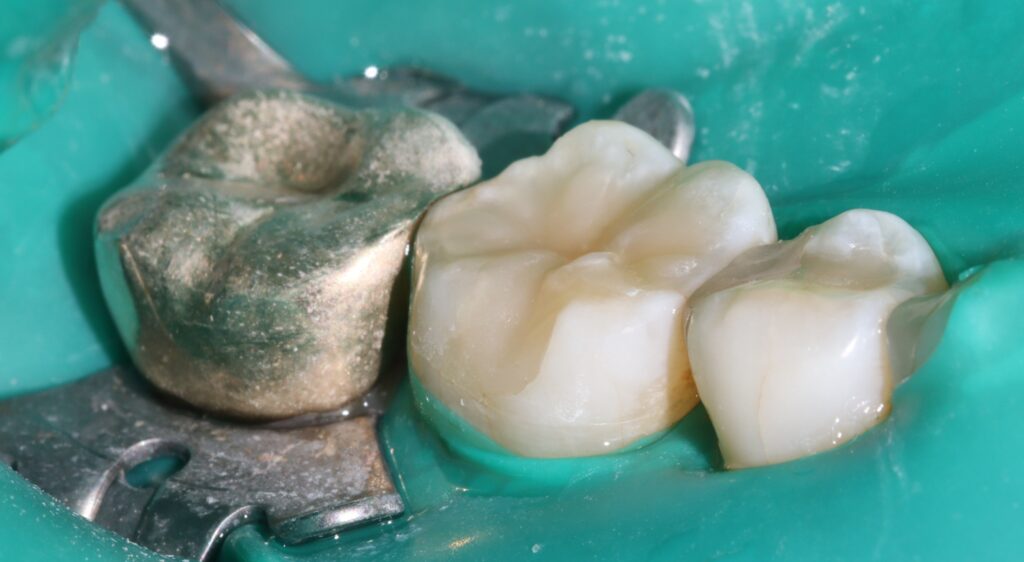

손상된 부위를 정리한 뒤 접착 과정을 거쳐

복합레진을 여러 층으로 쌓아 올리며

치아 형태를 재구성하는 방식으로

진행되기 때문인데요.

이 과정에서는 치아의 교합 높이와

인접 치아와의 관계까지 고려해야 해

치아 구조에 대한 이해와 세밀한 조정이 필요합니다.